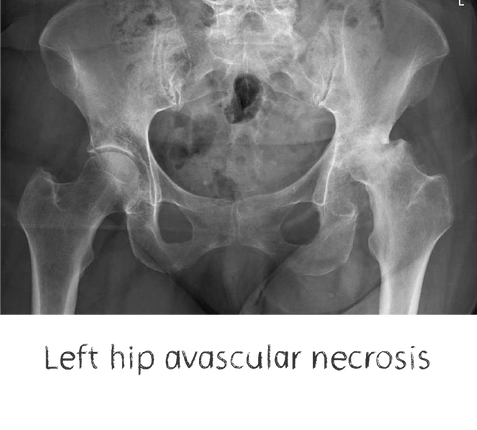

Plain film x-rays are taken to assess the joint

These are usually taken prior to your appointment. These help to confirm the diagnosis, assess the wear pattern and look for particular deformities. They can show old metalware and its position in the bone.

Sometimes the history and exam may suggest a particular disease process that is not seen on X-Rays. Focal cartilage defects, meniscal pathology, synovitis are better appreciated on MR imaging.